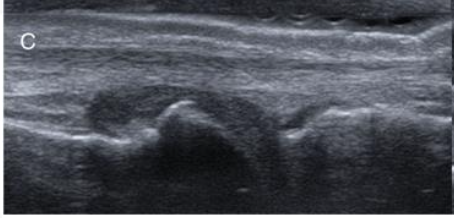

What grade is the synovial hypertrophy?

Grade 0

Grade this synovial hypertrophy

Grade 1: minimal within imaginary line between joint edges

Grade 2: moderate, extends over joint line with concave appearance

Grade 3: severe, extends beyond joint line with convex appearance